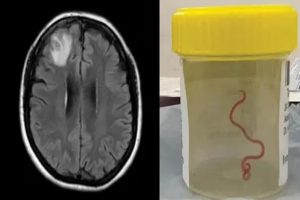

महिला में निमोनिया, पेट दर्द, दस्त, सूखी खांसी, बुखार और रात को पसीना आने जैसे तमाम लक्षण दिख रहे थे। डॉक्टर साल 2021 से ही उसका स्टेरॉयड और अन्य दवाओं से इलाज कर रहे हैं। 2022 में महिला में डिप्रेशन और भूलने की बीमारी के लक्षण भी दिखने लगे, जिसके बाद डॉक्टरों ने उसके मस्तिष्क का एमआरआई स्कैन किया, जिसमें कुछ गड़बड़ी का पता चला। फिर सर्जरी करने की सलाह दी गई, लेकिन बाद में उन्हें पता चला कि मस्तिष्क में जिंदा कीड़ा है।

सर्जिकल टीम को जो मिला वो 3 इंच लंबा, चमकीले लाल रंग का, पैरासाइट राउंडवर्म था, जिसे वैज्ञानिक ओफिडास्करिस रोबर्टसी के नाम से जानते हैं। ये महिला के मस्तिष्क में रेंग रहा था। इसका मिलना इसलिए भी अजीब बात है क्योंकि ये आमतौर पर सांपों में पाया जाता है, इंसानों में नहीं। ये विशेष तरह का राउंडवॉर्म (कीड़ा) कार्पेट पायथंस में पाया जाता है, जो कंस्ट्रिक्टर की एक बड़ी प्रजाति है। ये ऑस्ट्रेलिया, इंडोनेशिया और पापुआ न्यू गिनी में पाई जाती है।